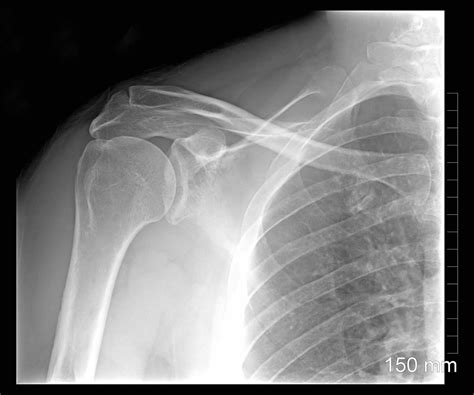

Diagnosing problems with the epiphysis typically involves a combination of physical examinations, imaging studies, and sometimes, laboratory tests. When someone, especially a child or adolescent, presents with bone or joint pain, the diagnostic process usually begins with a thorough physical exam. Doctors will assess the range of motion, stability, and alignment of the affected joint. They’ll also look for signs of inflammation, such as swelling, redness, and tenderness to the touch. The location and nature of the pain can provide valuable clues about the underlying problem.

Imaging studies play a crucial role in visualizing the epiphysis and identifying any abnormalities. X-rays are often the first-line imaging modality, as they can reveal fractures, dislocations, and bone deformities. However, X-rays may not always be sufficient to visualize subtle cartilage or soft tissue injuries. In such cases, more advanced imaging techniques like magnetic resonance imaging (MRI) may be necessary. MRI provides detailed images of the epiphysis, including the growth plate, articular cartilage, and surrounding soft tissues. This can help diagnose conditions like osteochondritis dissecans, cartilage damage, and occult fractures that may not be visible on X-rays. In some cases, computed tomography (CT) scans may be used to assess complex fractures or bone tumors involving the epiphysis. CT scans provide cross-sectional images of the bone, allowing for precise evaluation of fracture patterns and bone structure. Additionally, laboratory tests may be ordered to rule out infections or inflammatory conditions that can affect the epiphysis. Blood tests can help detect elevated white blood cell counts, inflammatory markers, or abnormal levels of calcium, phosphate, or vitamin D. In summary, diagnosing epiphyseal problems requires a comprehensive approach that integrates clinical findings with imaging and laboratory data. This allows healthcare professionals to accurately identify the underlying cause of the problem and develop an appropriate treatment plan. Getting the right diagnosis is the first step towards effective management and preventing long-term complications!